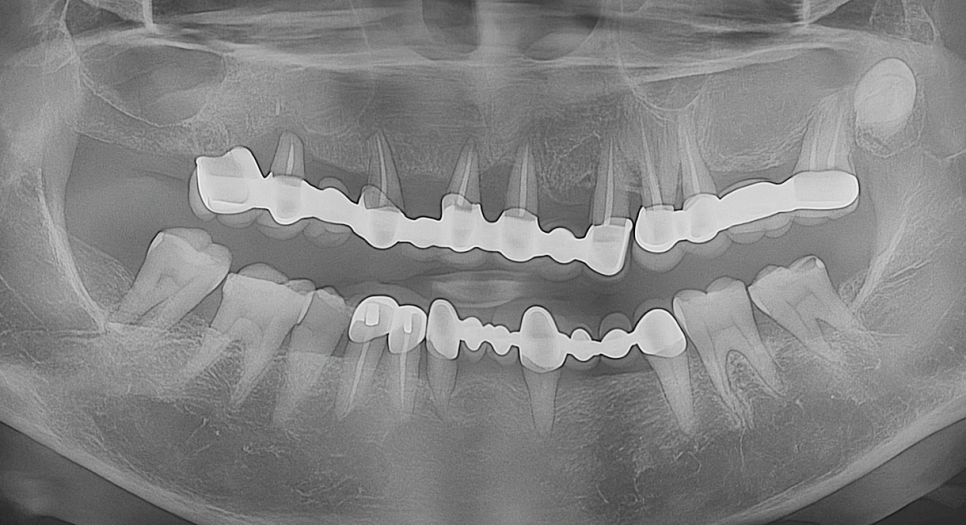

✔ 기본 검사

엑스레이 촬영을 통해 상악의

전체적인 치아와 뼈 상태를 확인합니다.

기존 치아들의 치료 가능성을 평가하고

풀아치 임플란트가 적절한 치료 방법인지

판단합니다.

✔ 정밀 진단

심한 충치, 치주 질환, 치아 파절 등으로

개별 치료가 어렵거나 예후가 불량한

경우 풀아치 임플란트를 고려합니다.